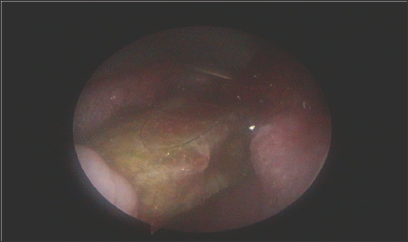

A 9 and 8 months old male infants; presented to our emergency unit (at two different occasions) within few hours after history of F.B swallow (Okra pods) given by their guardians with quite similar presentations like the first case. Immediate endoscopic extraction was done and Okra pod was successfully removed in both cases. In the third case, Okra was partially lodged in the nasopharynx (Figure 1) ; so, it was cut by scissors and removed in two pieces. After removal, examination revealed minor mucosal erosions (Figure 2) . Postoperatively, both infants were transferred to PICU. CXR and CT chest were done and revealed ground-glass opacity with interlobular sepal thickening in the middle and lower lobes of both lungs (Figure 3). Aspiration pneumonia was diagnosed. Treatment regimen included systemic steroid, oxygen therapy, antibiotics and raceme nebulizer. Marked improvement of their chest condition up for one month then monthly for 3 months revealed nothing was observed and oral feeding started within 2 days. They were abnormal as regard their clinical and radiological examination [1]. discharged one week after PICU admission. Regular weekly follow up for one month then monthly for 3 months revealed nothing abnormal as regard their clinical and radiological examination [1].

Figure 1: Okra pod is filling or pharynx with upper part passing behind uvula and lower end in post-cricoids area.

Figure 2: Mucosal erosions in or pharynx and post-cricoids after FB removal.